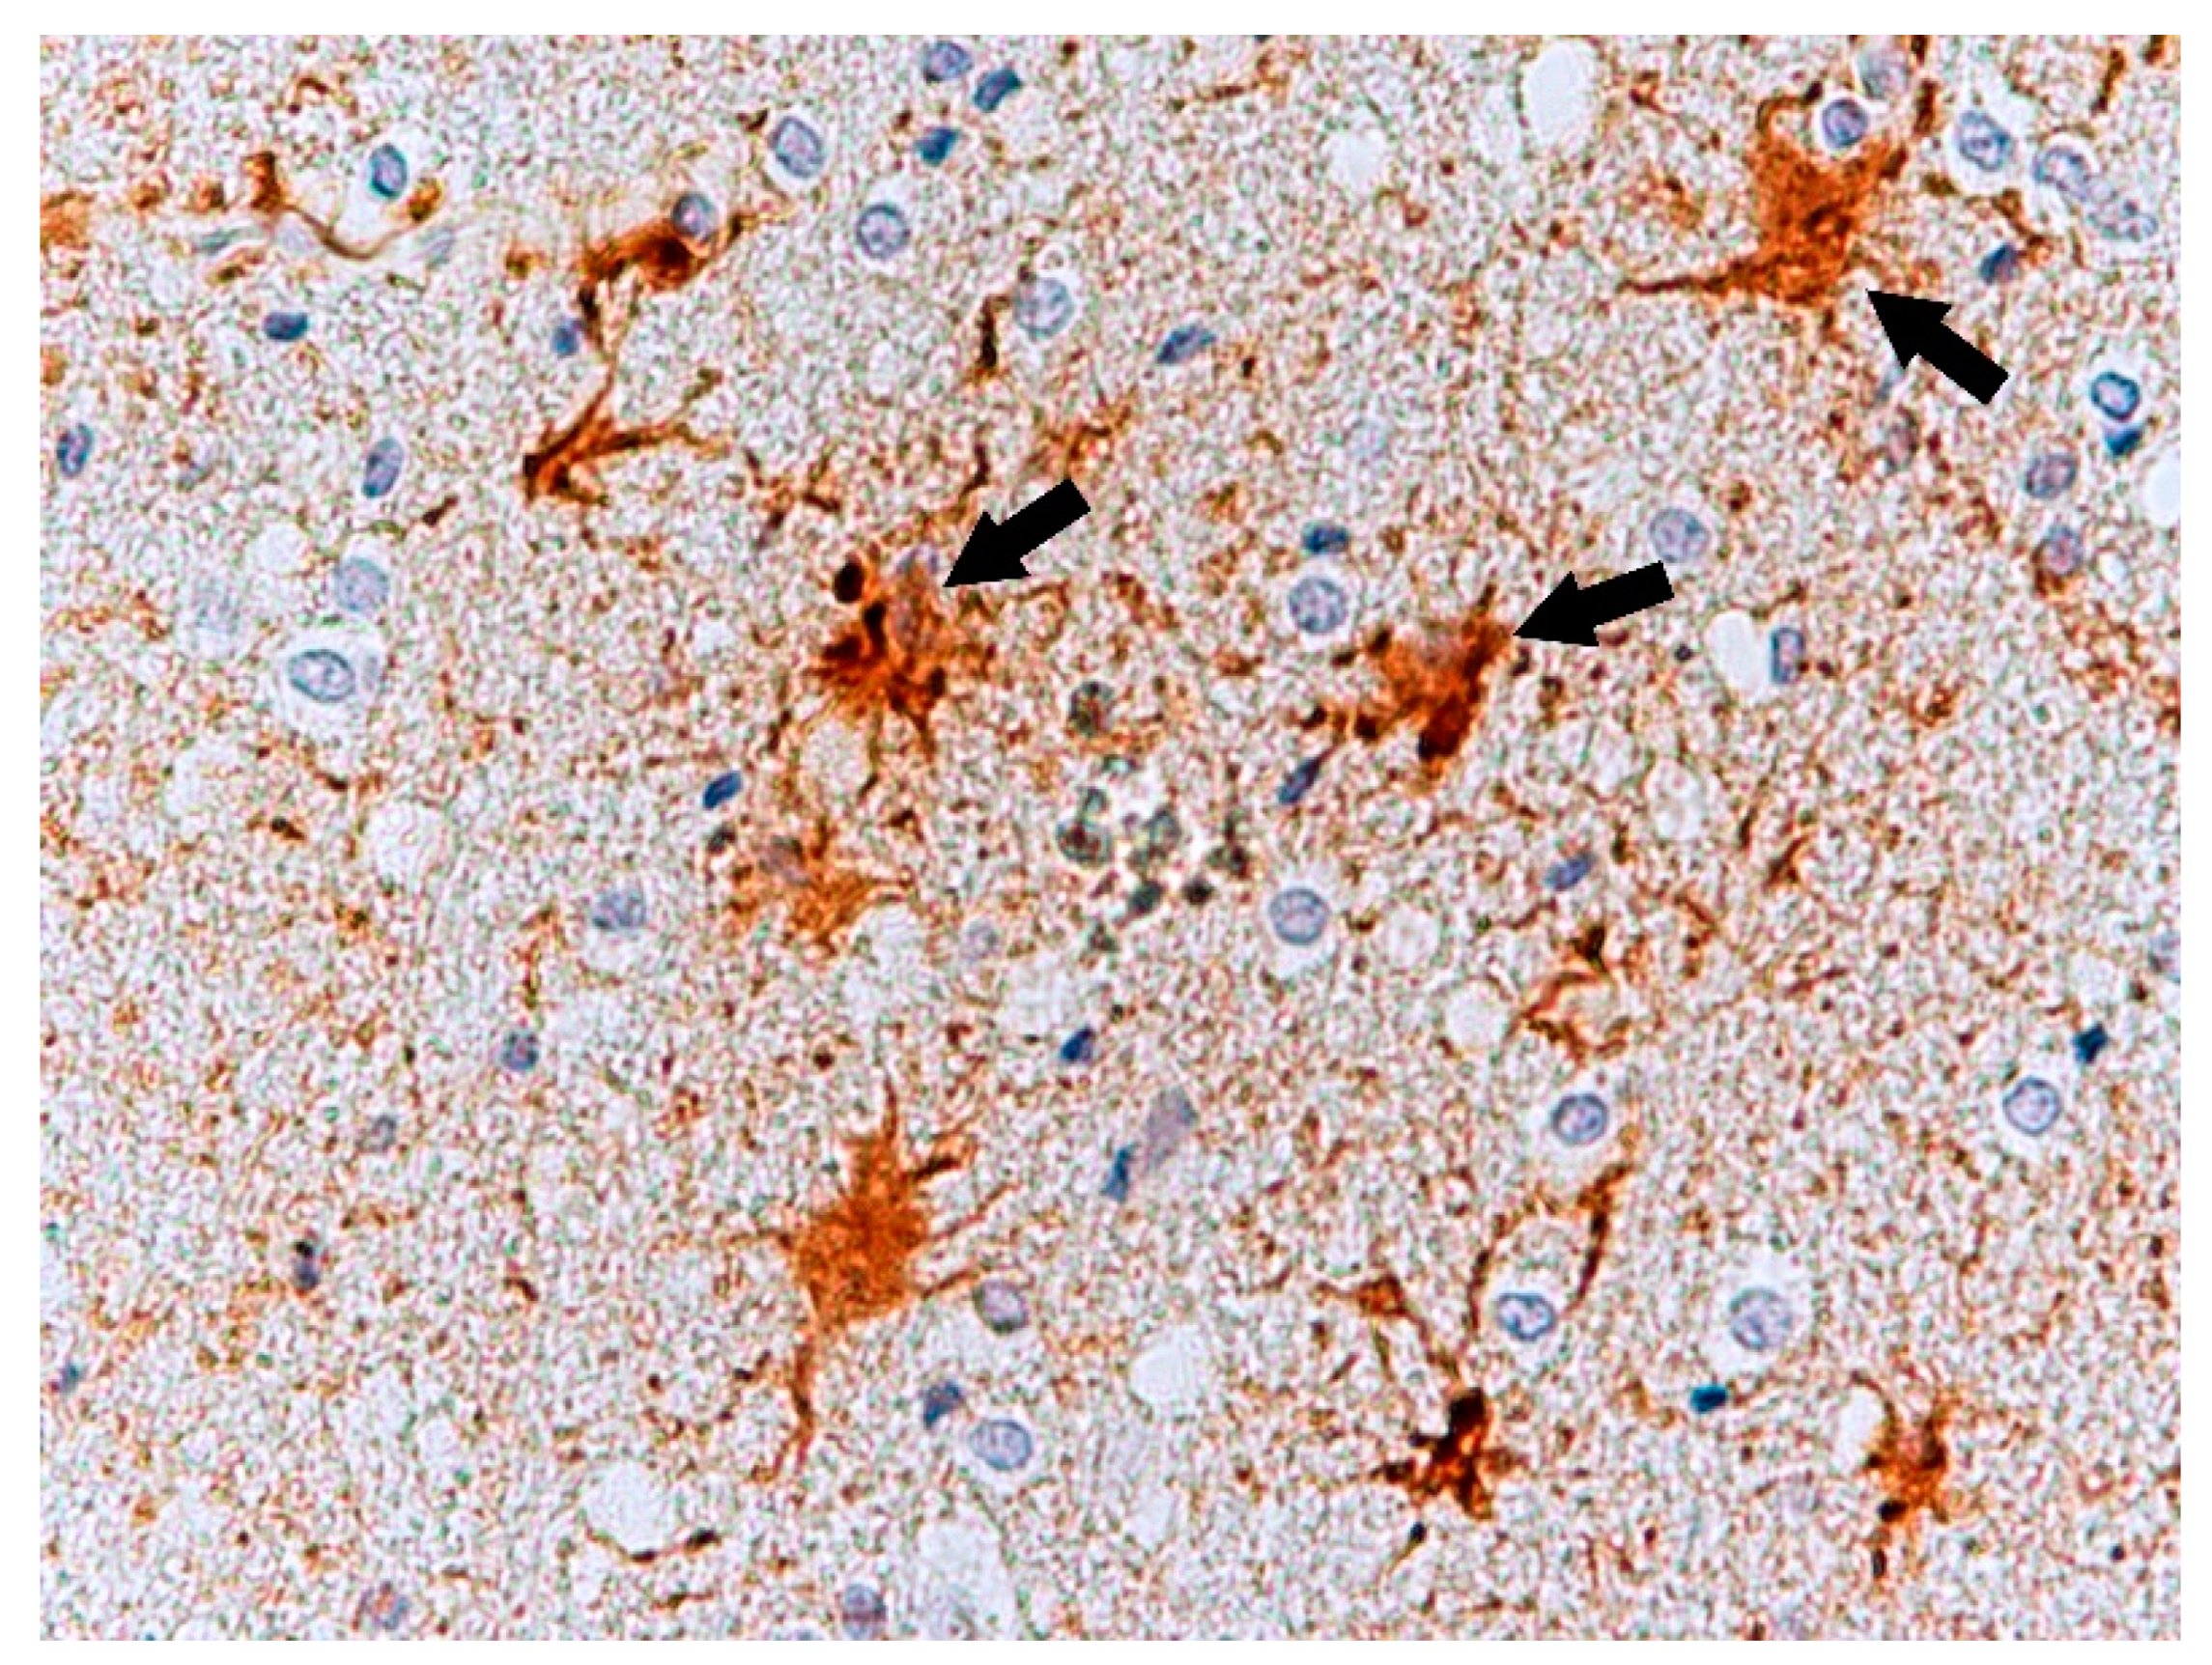

Histochemical Methods